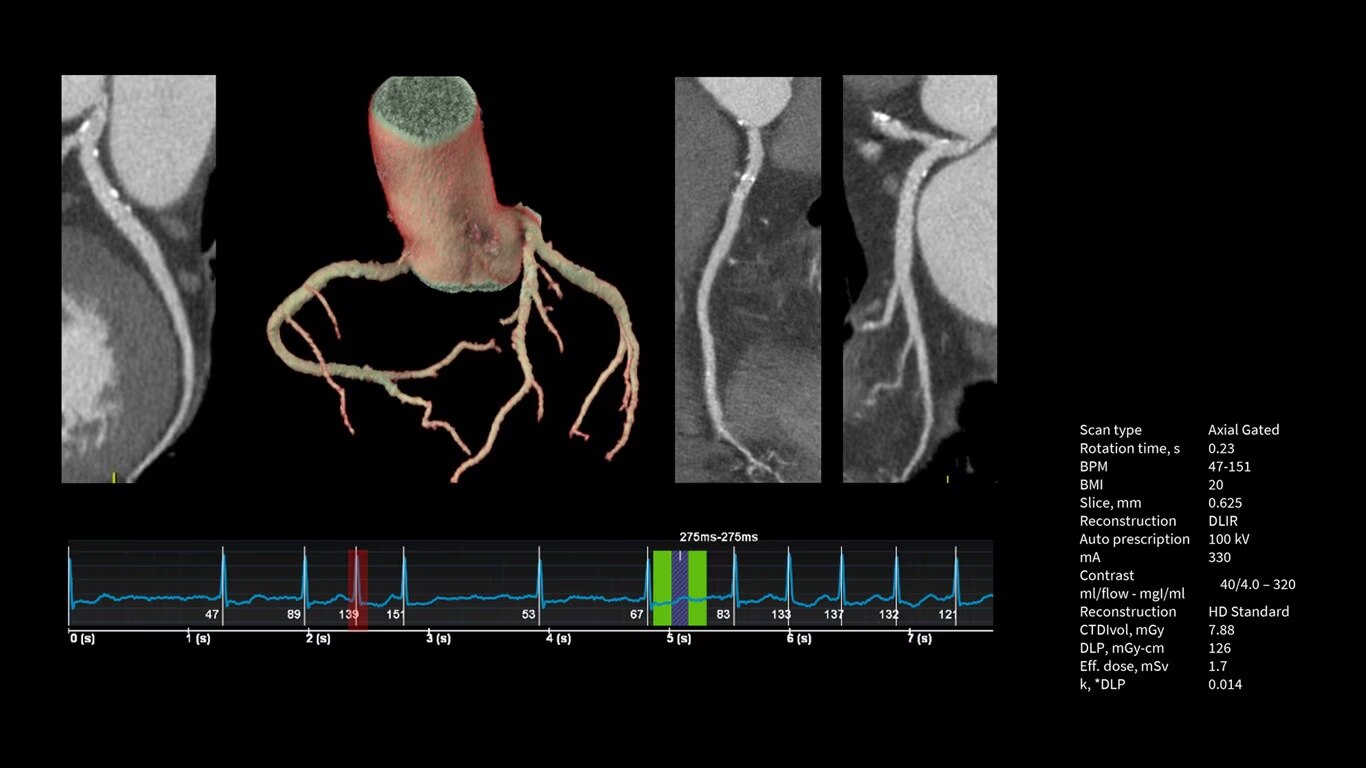

Upgrade to the industry's fastest rotation time

The Revolution Apex platform allows you to upgrade your gantry rotation speed. You can start with 0.28 sec gantry rotation time, and at any point in time when you need to advance your cardiac capability, you can upgrade to 0.23 seconds per rotation with the industry’s fastest rotation time.